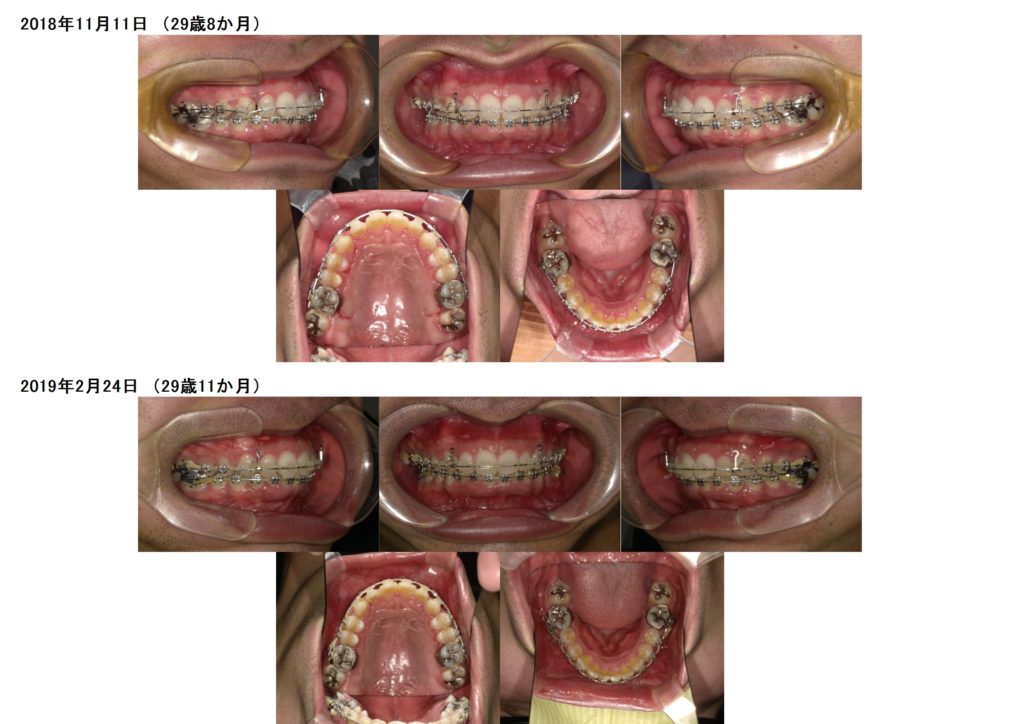

上下の口腔内写真を見比べていただくと、約半年ほどで下のガタガタしていた歯並びが徐々に治っているのが分かると思います。

そこからさらに5か月ぐらいでガタガタは改善され、噛み合わせの調整に入りました。

噛み合わせの調整期間はとてもじれったい期間かもしれません。見た目はキレイに並んだのにな~、まだ先生外せない?なんてお声もありますが、ここからが一番重要なんです。

コツコツととっても地味な作業なんで、患者様からはあまり変わってないように見えるかもしれませんが、しっかりと噛み合わせをあわせるためなんです。